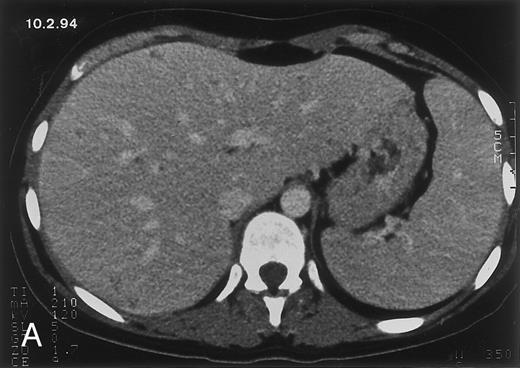

Radiologic evolution in patient B. (A) Postcontrast abdominal CT scan on February 10, 1994 shows multiple small hypodense areas in all segments of the liver suggestive of hepatic candidiasis. Twenty-four days previously, the patient had recovered from severe neutropenia after the second cycle of chemotherapy for ALL. (B) On May 4, 16 days after the neutrophil count had dropped below 500/μL in the third chemotherapy cycle, there is clear improvement of the radiologic findings, with only a few hypodense areas in the liver.

(C) On June 6, 31 days after normalization of neutrophils, CT again shows multiple lesions in the liver (arrowheads) with a different presentation: the small lesions show strong peripheral enhancement. (D) On September 2, 129 days after neutrophil recovery, all hepatic lesions have completely resolved.

Evolution of fungal lesions on CT scans during and after neutropenia is summarized in Table 2. Figure 1 (patient A) and Fig 2 (patient B) serve to illustrate Table 2.

In three patients, multiple round lesions were seen on postcontrast CT scans of the abdomen in the liver and the spleen, while in two cases, lesions could only be seen in the liver (Table 2). Following the diagnosis of disseminated candidiasis, these lesions decreased in size and visibility during subsequent neutropenia in three patients (compare Fig 2A and B) and disappeared completely in two patients (compare Fig 1A and B). The numbers of days of severe neutropenia (neutrophils <500/μL) at the time the CT scan was performed are listed in Table 2. After recovery from neutropenia and despite continued antifungal therapy, the size and visibility of the lesions increased again (Fig 1C). Similarly, the number of days since recovery from severe neutropenia (neutrophils >500/μL) are listed in Table 2. In two of three patients treated with another cycle of myeloablative chemotherapy, this waxing and waning pattern of radiologic lesions could be seen again (Fig 1D and E). In all patients, lesions eventually disappeared (Figs 1F and 2D) after prolonged antifungal therapy.